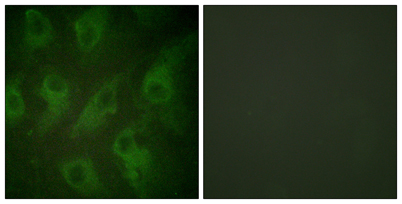

| Dilutions: | Western Blot: 1/500 - 1/2000. Immunohistochemistry: 1/100 - 1/300. Immunofluorescence: 1/200 - 1/1000. ELISA: 1/10000. Not yet tested in other applications. |